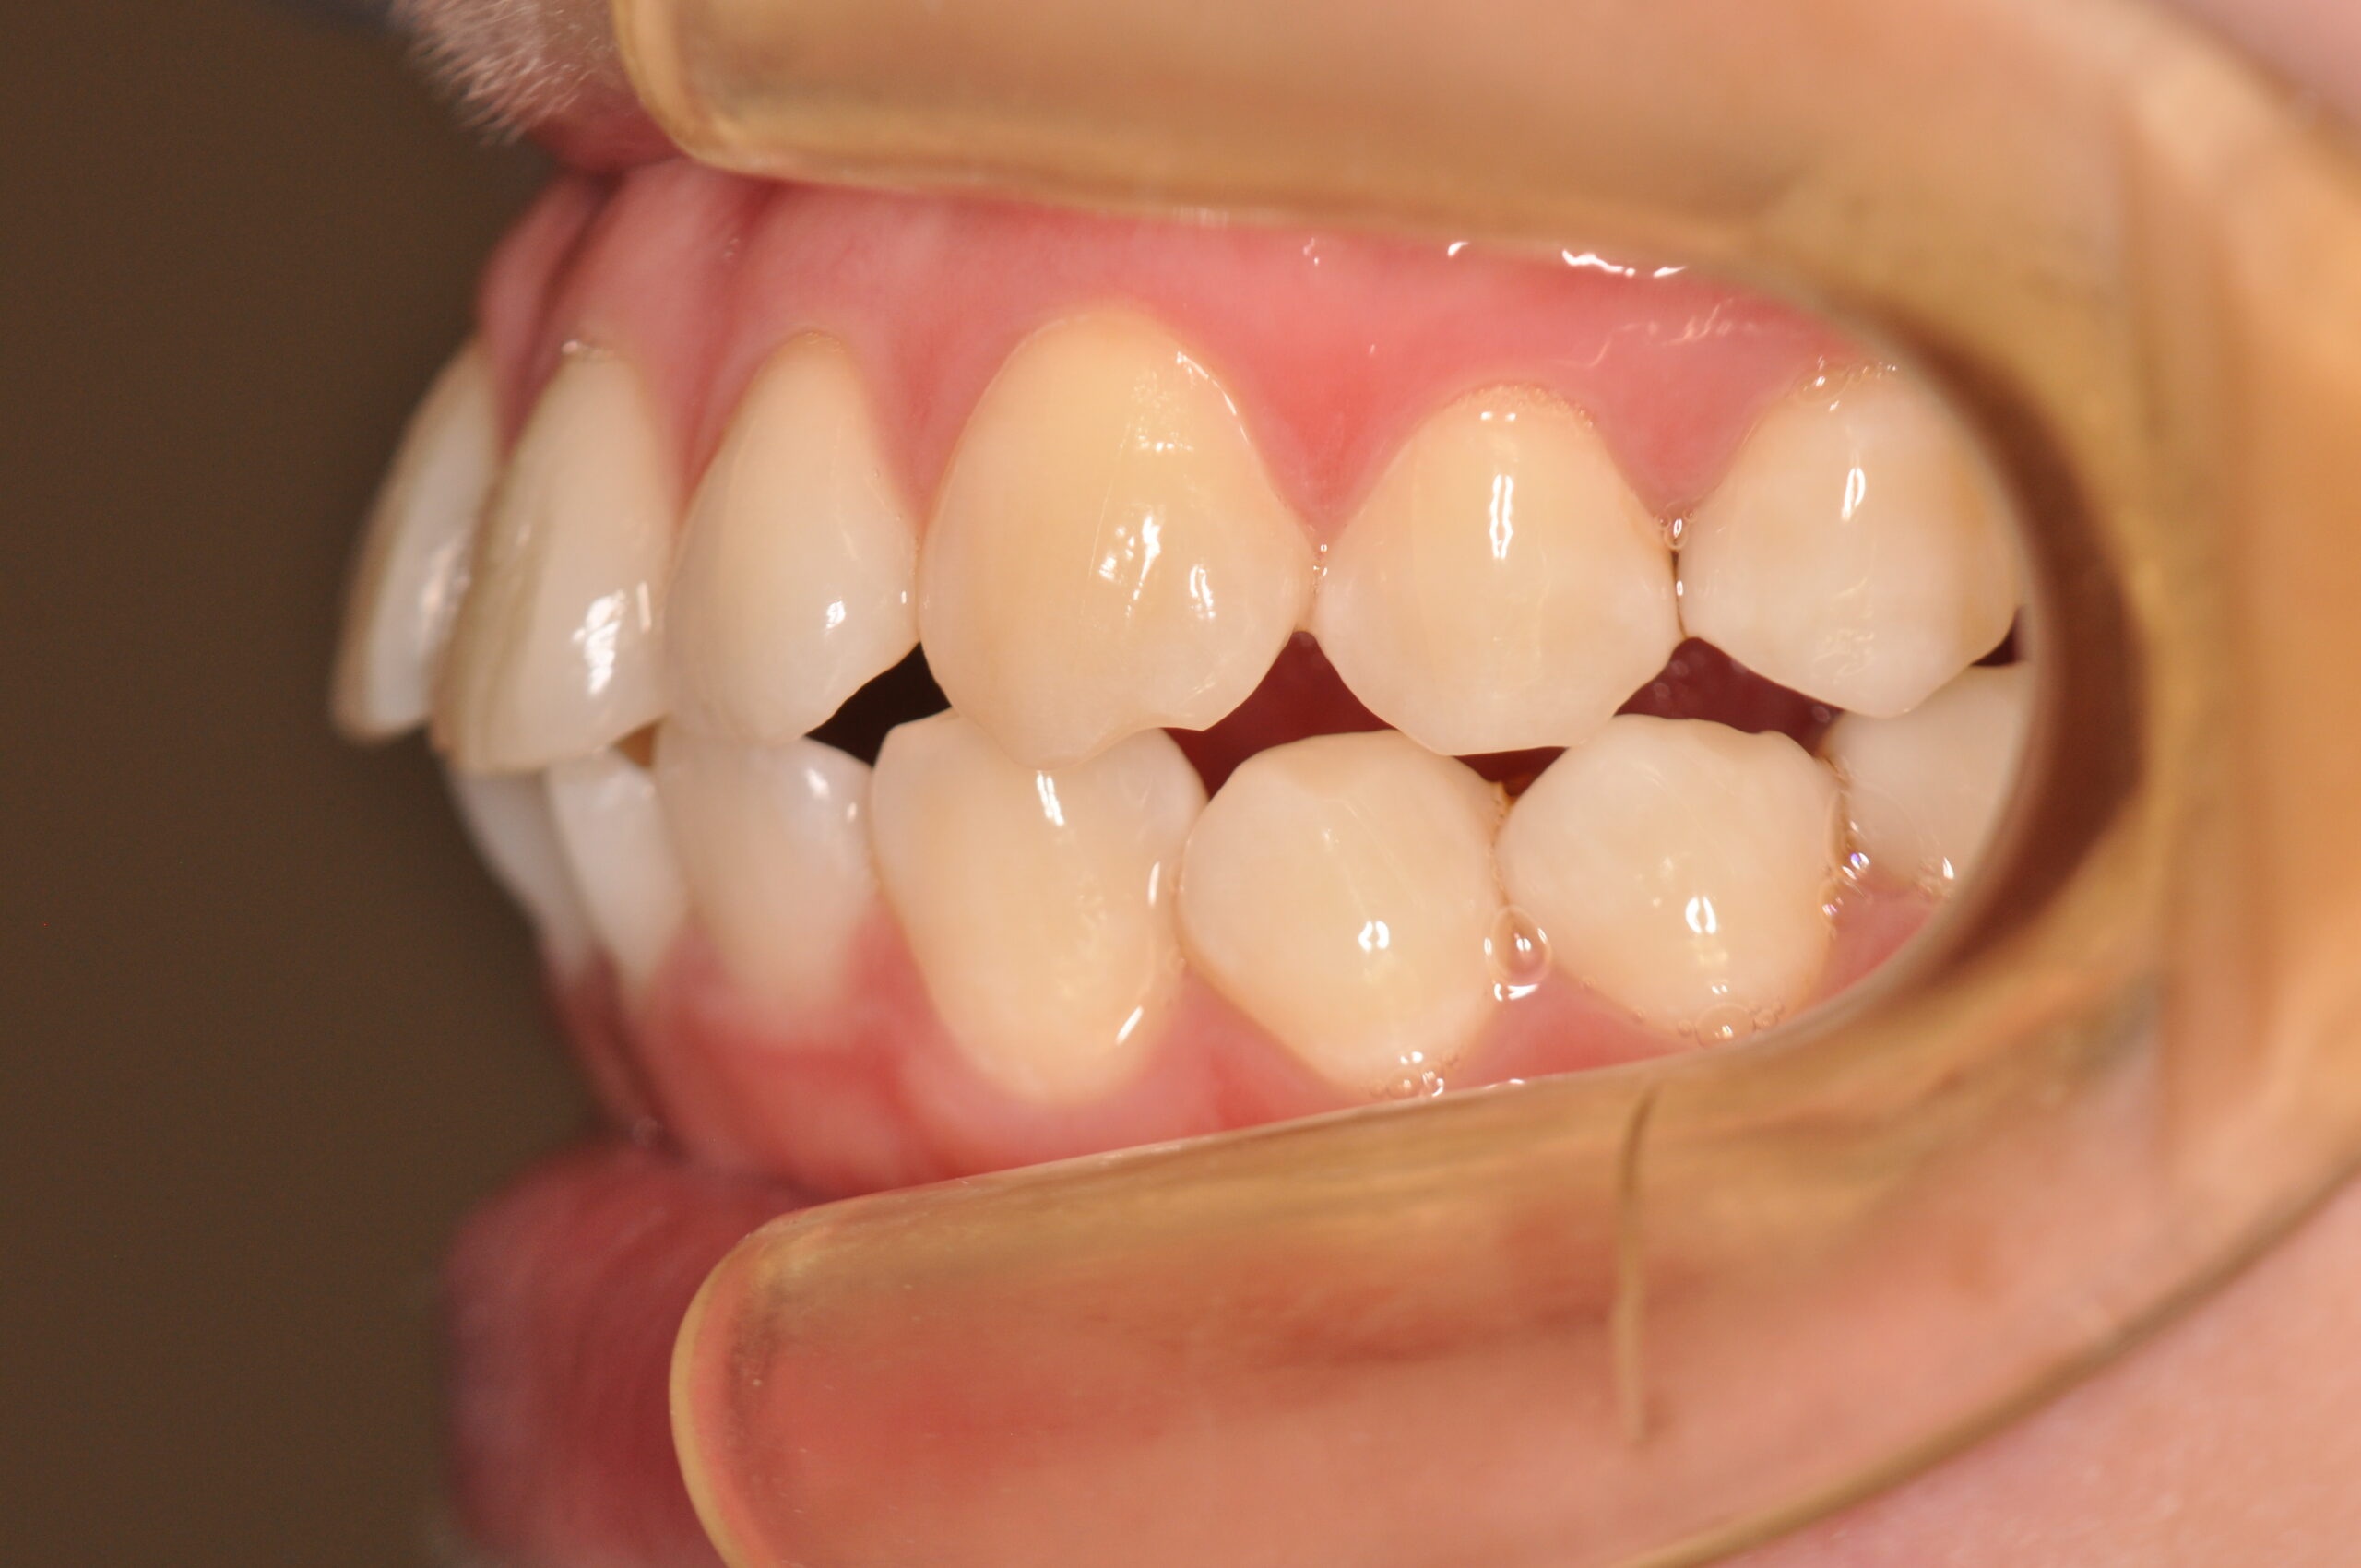

| 治療内容の詳細 | 初診時29歳の女性で、出っ歯を気にされ来院されました。 検査の結果、上顎前突を伴うアングルⅡ級1類不正咬合と診断しました。 治療としては、上顎左右第1小臼歯および下顎左右第2小臼歯をして、セルフライゲーションブラケット装置(デーモンシステム)で歯の配列を行いました。 同時に顎間ゴムにて咬合関係の改善を行いました。 この際、上顎に歯科矯正用アンカースクリューを設置し上顎前歯部後退時の土台としました。 治療期間は、2年6ヶ月でした。 |